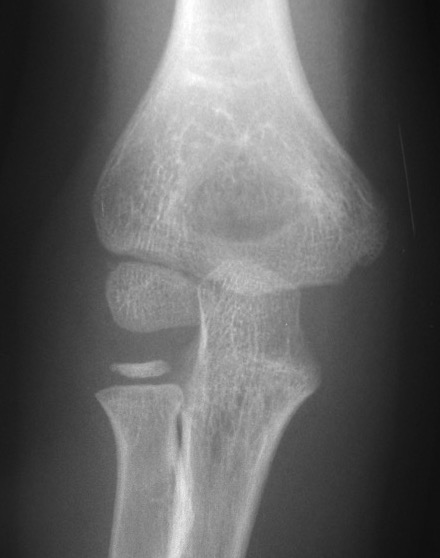

X-ray

Undisplaced

- typically metaphyseal flake

- looks minimally displaced on AP and lateral

- perform an internal oblique x-ray to exclude displacement

Displaced